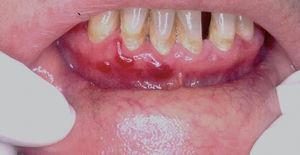

Una mujer de 60 años tenía historia de erosiones y ampollas en encías y en mucosa yugal desde hacía varios años. La paciente había sido diagnosticada de herpes simple recidivante, sin mejorar con la administración de antiviriásicos. En la exploración física la paciente presentaba eritema de encía superior e inferior, con aparición ocasional de ampollas (fig. 1). No presentaba lesiones en otras localizaciones. Los estudios realizados nos llevaron al diagnóstico de PM 8. Inicialmente se pautó acetónido de triamcinolona al 0,1 % cuando la paciente tuviera los brotes. Aunque cada uno se controlaba, al ser éstos más frecuentes, se decidió pautar tratamiento con dapsona 100 mg/día (niveles de glucosa 6-fosfato-deshidrogenasa [G6PD] normales) junto a 800 mg/día de vitamina E. En la actualidad la paciente está asintomática y, aunque en alguna ocasión ha presentado mínimos brotes, suelen durar 2 o 3 días y desaparecen de manera espontánea. No ha presentado nuevas lesiones después de 5 años de seguimiento.

Fig. 1.--Eritema en mucosa gingival asociado a ampollas (paciente 1).